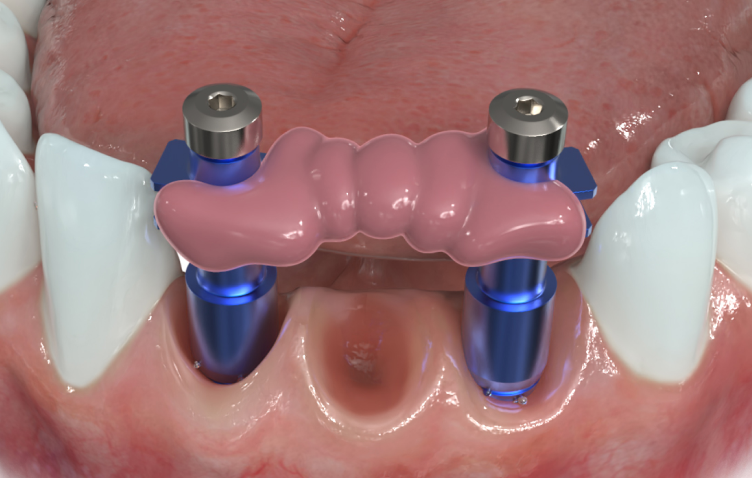

Verbindung zwischen mehreren Implantat-Übertragungspfosten

Verwenden Sie J-Temp zur Verbindung zwischen mehrerer Implantat-Übertragungspfosten oder mit einer Zahnseide-Verstärkungstechnik, um eine Dimensionsänderung bei der Abformung zu verhindern.